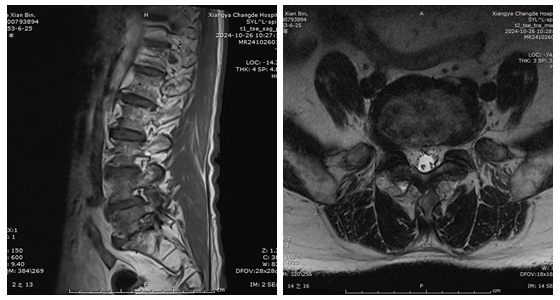

近日,湘雅常德医院骨科(脊柱外科)团队成功为一名老年腰椎间盘突出症患者应用关节镜辅助单孔脊柱手术(AUSS)实施了“内镜下腰椎间盘髓核切除+椎间孔扩大减压术”。 71岁...